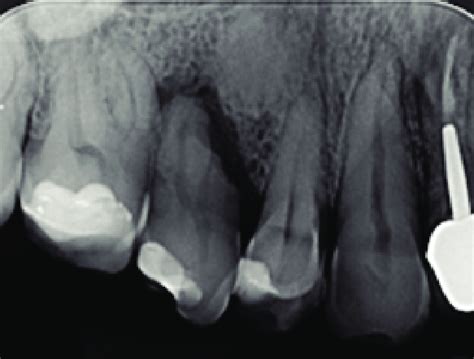

Imagen radiográfica de un quiste radicular.